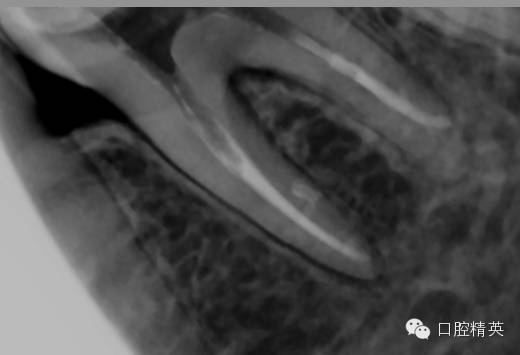

tf镍钛锉预备至30#06锥度(虽然根尖区域的预备应该在35#~40#)但我认为这不是根尖周炎,所以仅仅预备到30#,大量次氯酸钠荡洗根管,根充还是用的iroot糊剂和热牙胶,我用的是思博安的热牙胶,很多同行和我说,相比韩国的产品思博安的成本太高了,但思博安的牙胶是 β象限的,低温时的流动性更好,更容易进入狭窄部位和侧支根管,所以我认为,相对与更好的治疗效果,成本并不重要。

近中根管的侧枝清晰可见

![36的一次性根充]()